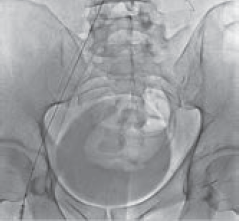

Рис. 5. Баллонная ангиопластика левой общей и левой наружной подвздошных вен пациента М., 39 лет, от 28.03.2017. Оперативный доступ из левой подколенной вены. Положение пациента на животе

Рис. 6. Имплантация одного стента в левую общую и левую наружную подвздошную вены пациента М., 39 лет, от 28.03.2017. Оперативный доступ из левой подколенной вены. Положение пациента на животе

Рис. 7. Постдилятация стентированного сегмента левой общей подвздошной вены пациента М., 39 лет, от 28.03.2017. Оперативный доступ из левой подколенной вены. Положение пациента на животе

Рис. 8. Постдилятация стентированного сегмента левой наружной подвздошной вены пациента М., 39 лет, от 28.03.2017. Оперативный доступ из левой подколенной вены. Положение пациента на животе

Рис. 9. Контрольная флебография пациента М., 39 лет, от 28.03.2017. Оперативный доступ из левой подколенной вены. Положение пациента на животе. Проходимость обеих подвздошных вен и отсутствие коллатерального кровообращения